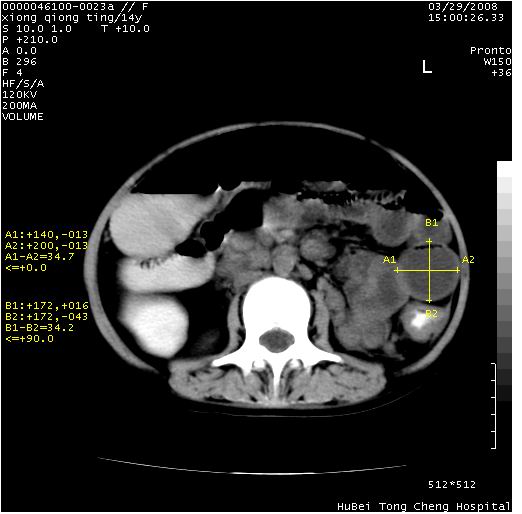

患儿 女,14岁。不规则发热一周,偶感头痛,无抽搐及呕吐。pe:神清,精神差,双侧瞳孔等大等圆,对光反射敏感,双肺未闻及明显啰音,心音有力,腹部触之似揉面感,下腹压痛,无反跳痛。

中下腹及盆腔ct轴位平扫+增强扫描(层厚10mm,螺距1.0,重建间隔10mm),图像如下:

(注:患儿检查当日上午9时口服胃肠道对比剂,下午3时许行ct扫描检查,未行对比剂直肠保留灌肠,检查当日患儿腹泻)

中下腹及盆腔ct轴位扫描(ps+ce)提示:腹部肠管明显充气扩张,并见数个不同宽度之气液平面;疑不全性肠梗阻或肠郁张。临床会诊考虑为患儿腹泻,肠郁张所致;后来未经特殊处理,患儿大便恢复正常,亦无腹胀。